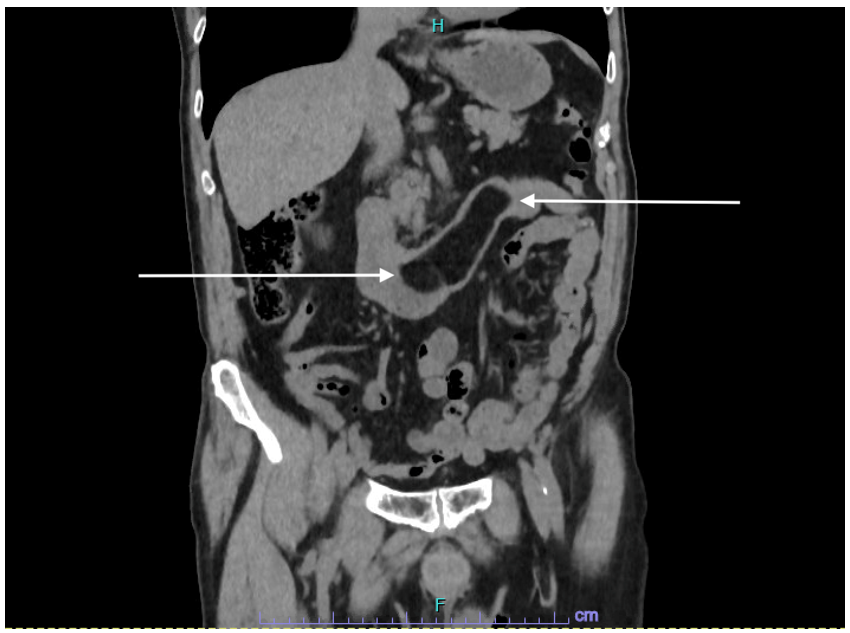

| Figure 1: Computed tomography of the abdomen - coronal section. The mass at the level of the duodenum measures -120 to -90 HU representing a duodenal lipoma, indicated with arrows |

Computed tomography (CT) of the abdomen confirmed the presence of a duodenal lipoma extending from the 2nd to 4th part of the duodenum, measuring 95 mm x 30 mm (Figure 1 - 3).

Computed tomography (CT) has grown in popularity for diagnostic purposes in the last decade. Lipomas are easily and reliably identified on CT because of their appearance as a smooth margined mass combined with a characteristic low uniform (fat density) attenuation with a low Hounsfield Unit (HU) count from -70 to -120 HU [28-30].